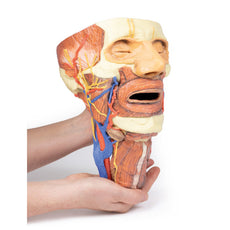

3D Printed Superficial Facial Nerves & Parotid Gland

3D Printed Superficial Facial Nerves & Parotid Gland

This 3D model presents the superficial anatomy of the face and head, and compliments the superficial facial anatomy

of our HW 44 model with a more expanded dissection across the scalp and occipital regions.

The superficial

neurovascular and muscular structures in the face largely mirror the structures described in reference to our HW 44

specimen (see description), although the terminal branches of the facial nerve (CNVII) can be largely followed

across a longer course from the parotid gland and the platysma muscle has been retained superficial to the mandible

and extends towards the neck.